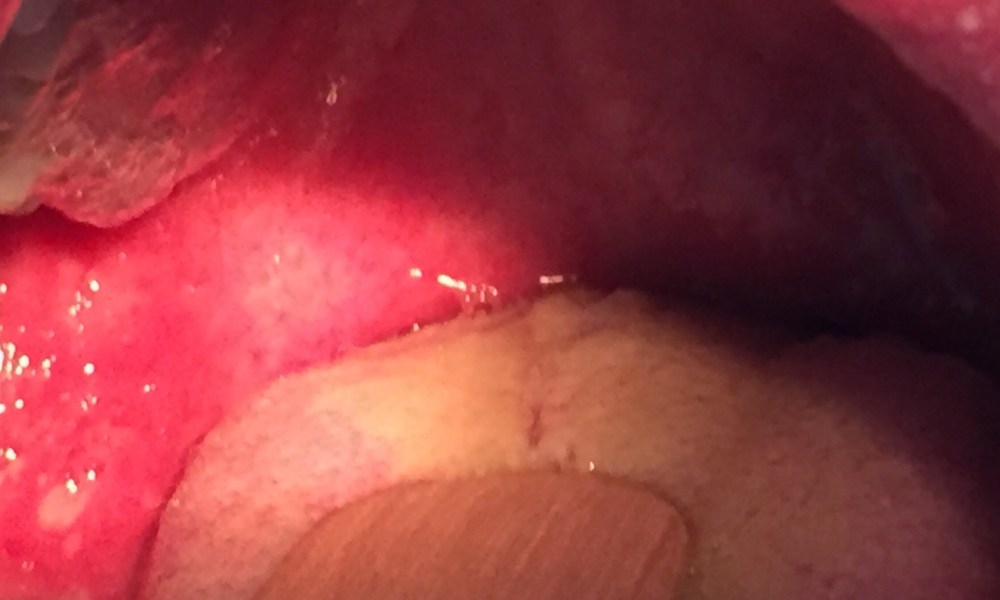

The diagnosis here is measles with a Koplik’s spot shown in the photo of the oral cavity. This is technically a clinical diagnosis, but due to the paucity of cases in Singapore, relatively few clinicians are likely to be confident in diagnosing this based on history and physical examination alone. Measles serology is unlikely to be positive within the first few days of illness, hence the way to confirm it would be to take a throat swab and send it for measles PCR test.